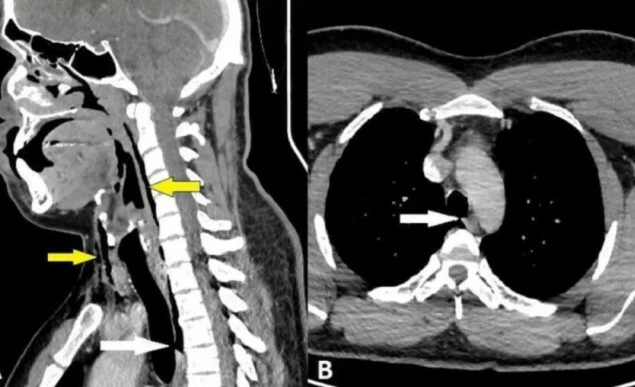

Hastaneye başvuran adama röntgen çekildiğinde doktorlar oldukça şaşırtıcı bir manzarayla karşı karşıya kaldılar. Adamın boğazında yırtıklar olduğu, akciğerlerinin arasındaki boşlukta da hava biriktiği anlaşıldı.